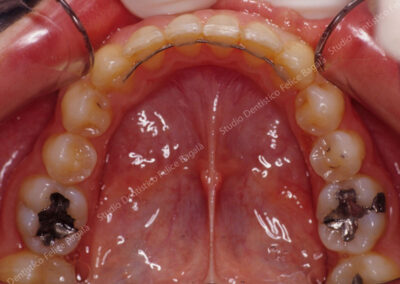

IL CASO DI MICHELA (ORTODONZIA CLASSICA)

Caso di adolescente trattata con ortodonzia fissa classica >con un tempo di cura di 16 mesi circa. Mancante per estrazione, da parte di un collega, il primo molare superiore a destra. Nelle foto di fine cura si vede lo spazio del molare completamente chiuso. Posteriormente a quel molare, a distanza di qualche anno, eromperà e verrà in arcata un altro molare, il dente del giudizio superiore destro. La paziente molto contenta di avere evitato il “rimpiazzo” di un dente mancante e aver acquisito un nuovo sorriso.